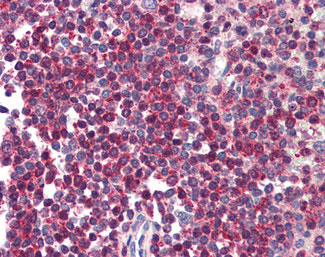

Anti-HTRA2 antibody IHC of human spleen. |